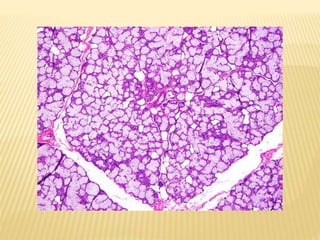

PAROTID GLAND